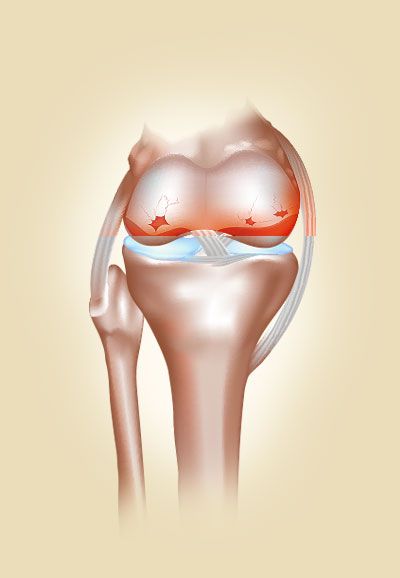

Дар фарқият аз баъзе бемориҳои дигар (маслан, бемориҳои хунукзада), бемории буғумҳо худ ба худ бартарф намешаванд, ин маънои онро дорад, ки бо мурури вақт дард фақат бештар мешавад ва боз ноҳинҷории бештареро ба бор меорад.

Агар ба буғумҳои дардманд фишор оварданро давом диҳед, беморӣ авҷ мегирад ва шояд чунин мавриде ба амал ояд, ки ҳатто тавассути табобати ҷарроҳӣ (консервативӣ) низ ҳолатро ислоҳ кардан ғайриимкон бошад.

Он барои тасмим гирифтан ба ҷарроҳии пуқиммат зарурат пеш меояд. Дар ҳолатҳои ҷудогона пурра ампутатсия кардани буғум зарур мешавад, ки ҳатман ба маъюбият бурда мерасонад.